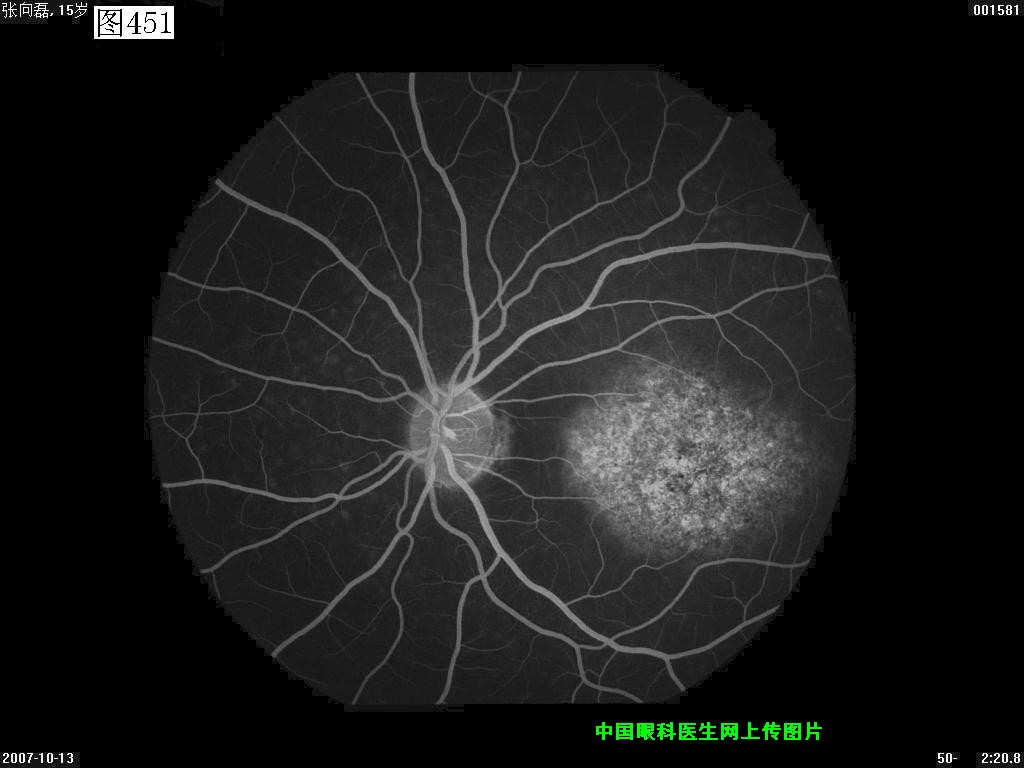

449 450 451 452